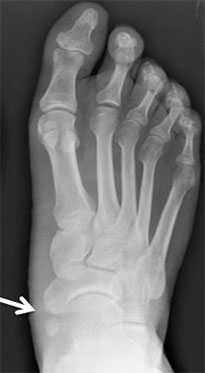

Добавочная ладьевидная кость классифицируется в соответствии с рентгенологическими ее особенностями:

- Сесамовидная косточка в толще сухожилия задней большеберцовой мышцы в области его прикрепления к ладьевидной кости

- Добавочная ладьевидная кость, сочленяющаяся синхондрозом с ладьевидной костью

- Костный выступ ладьевидной кости

Рентгенограммы стоп: 3 тип добавочной ладьевидной кости